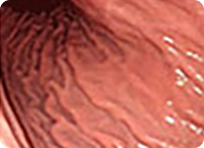

정상 위의 내시경 사진

최근 위내시경의 해상도는 아래 사진과 같이 아주 뛰어난 상태로 1mm이하의 작은 병변도 확대해서 관찰이 가능합니다. 따라서 내시경 검사는 정상과 별 차이가 없어 보이는 미세한 조기 위암과, 조기 식도암 및 조기 대장암을 진단하는데 가장 정밀하면서 정확한 방법입니다.

아래 사진과 같이 5x5mm 크기의 작은 사각형을 실제 17인치 모니터에 꽉 차 보일만큼 정확하게 확대해서 관찰할 수 있으며 1mm 눈금보다도 작은 부분도 정확하게 관찰할 수 있을 정도로 정확합니다.